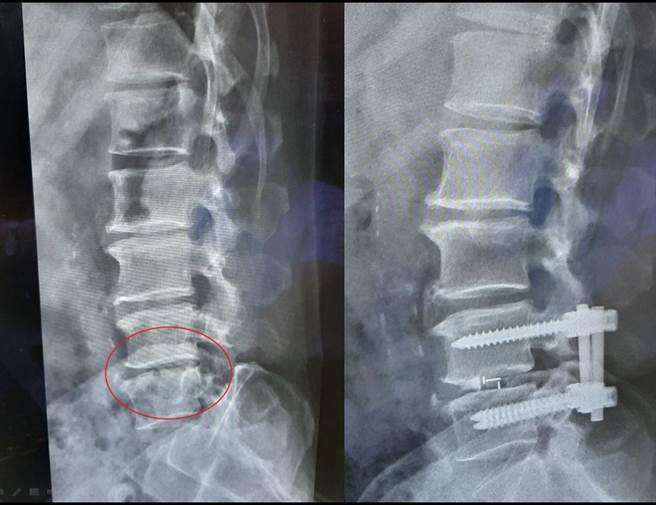

陈先生在1年多前因腰椎第4、5节椎间盘突出,在其他医院接受手术治疗,术后虽然症状有改善,但一段时间后在同一部位又再次復发。

曾仁河表示,当发生同一节段需要再次手术时,是无法再像第一次手术时只做椎间盘切除减压,否则会面临手术部位沾黏的问题,反而增加手术风险,因此改以健保给付的材料,进行微创骨融合手术为其治疗。

骨融合手术是将椎间盘挖除乾净后,在椎间盘的空间放一个垫片,并打钉子固定,不仅可以改善病人疼痛的问题,也能确保同一部位不再復发。